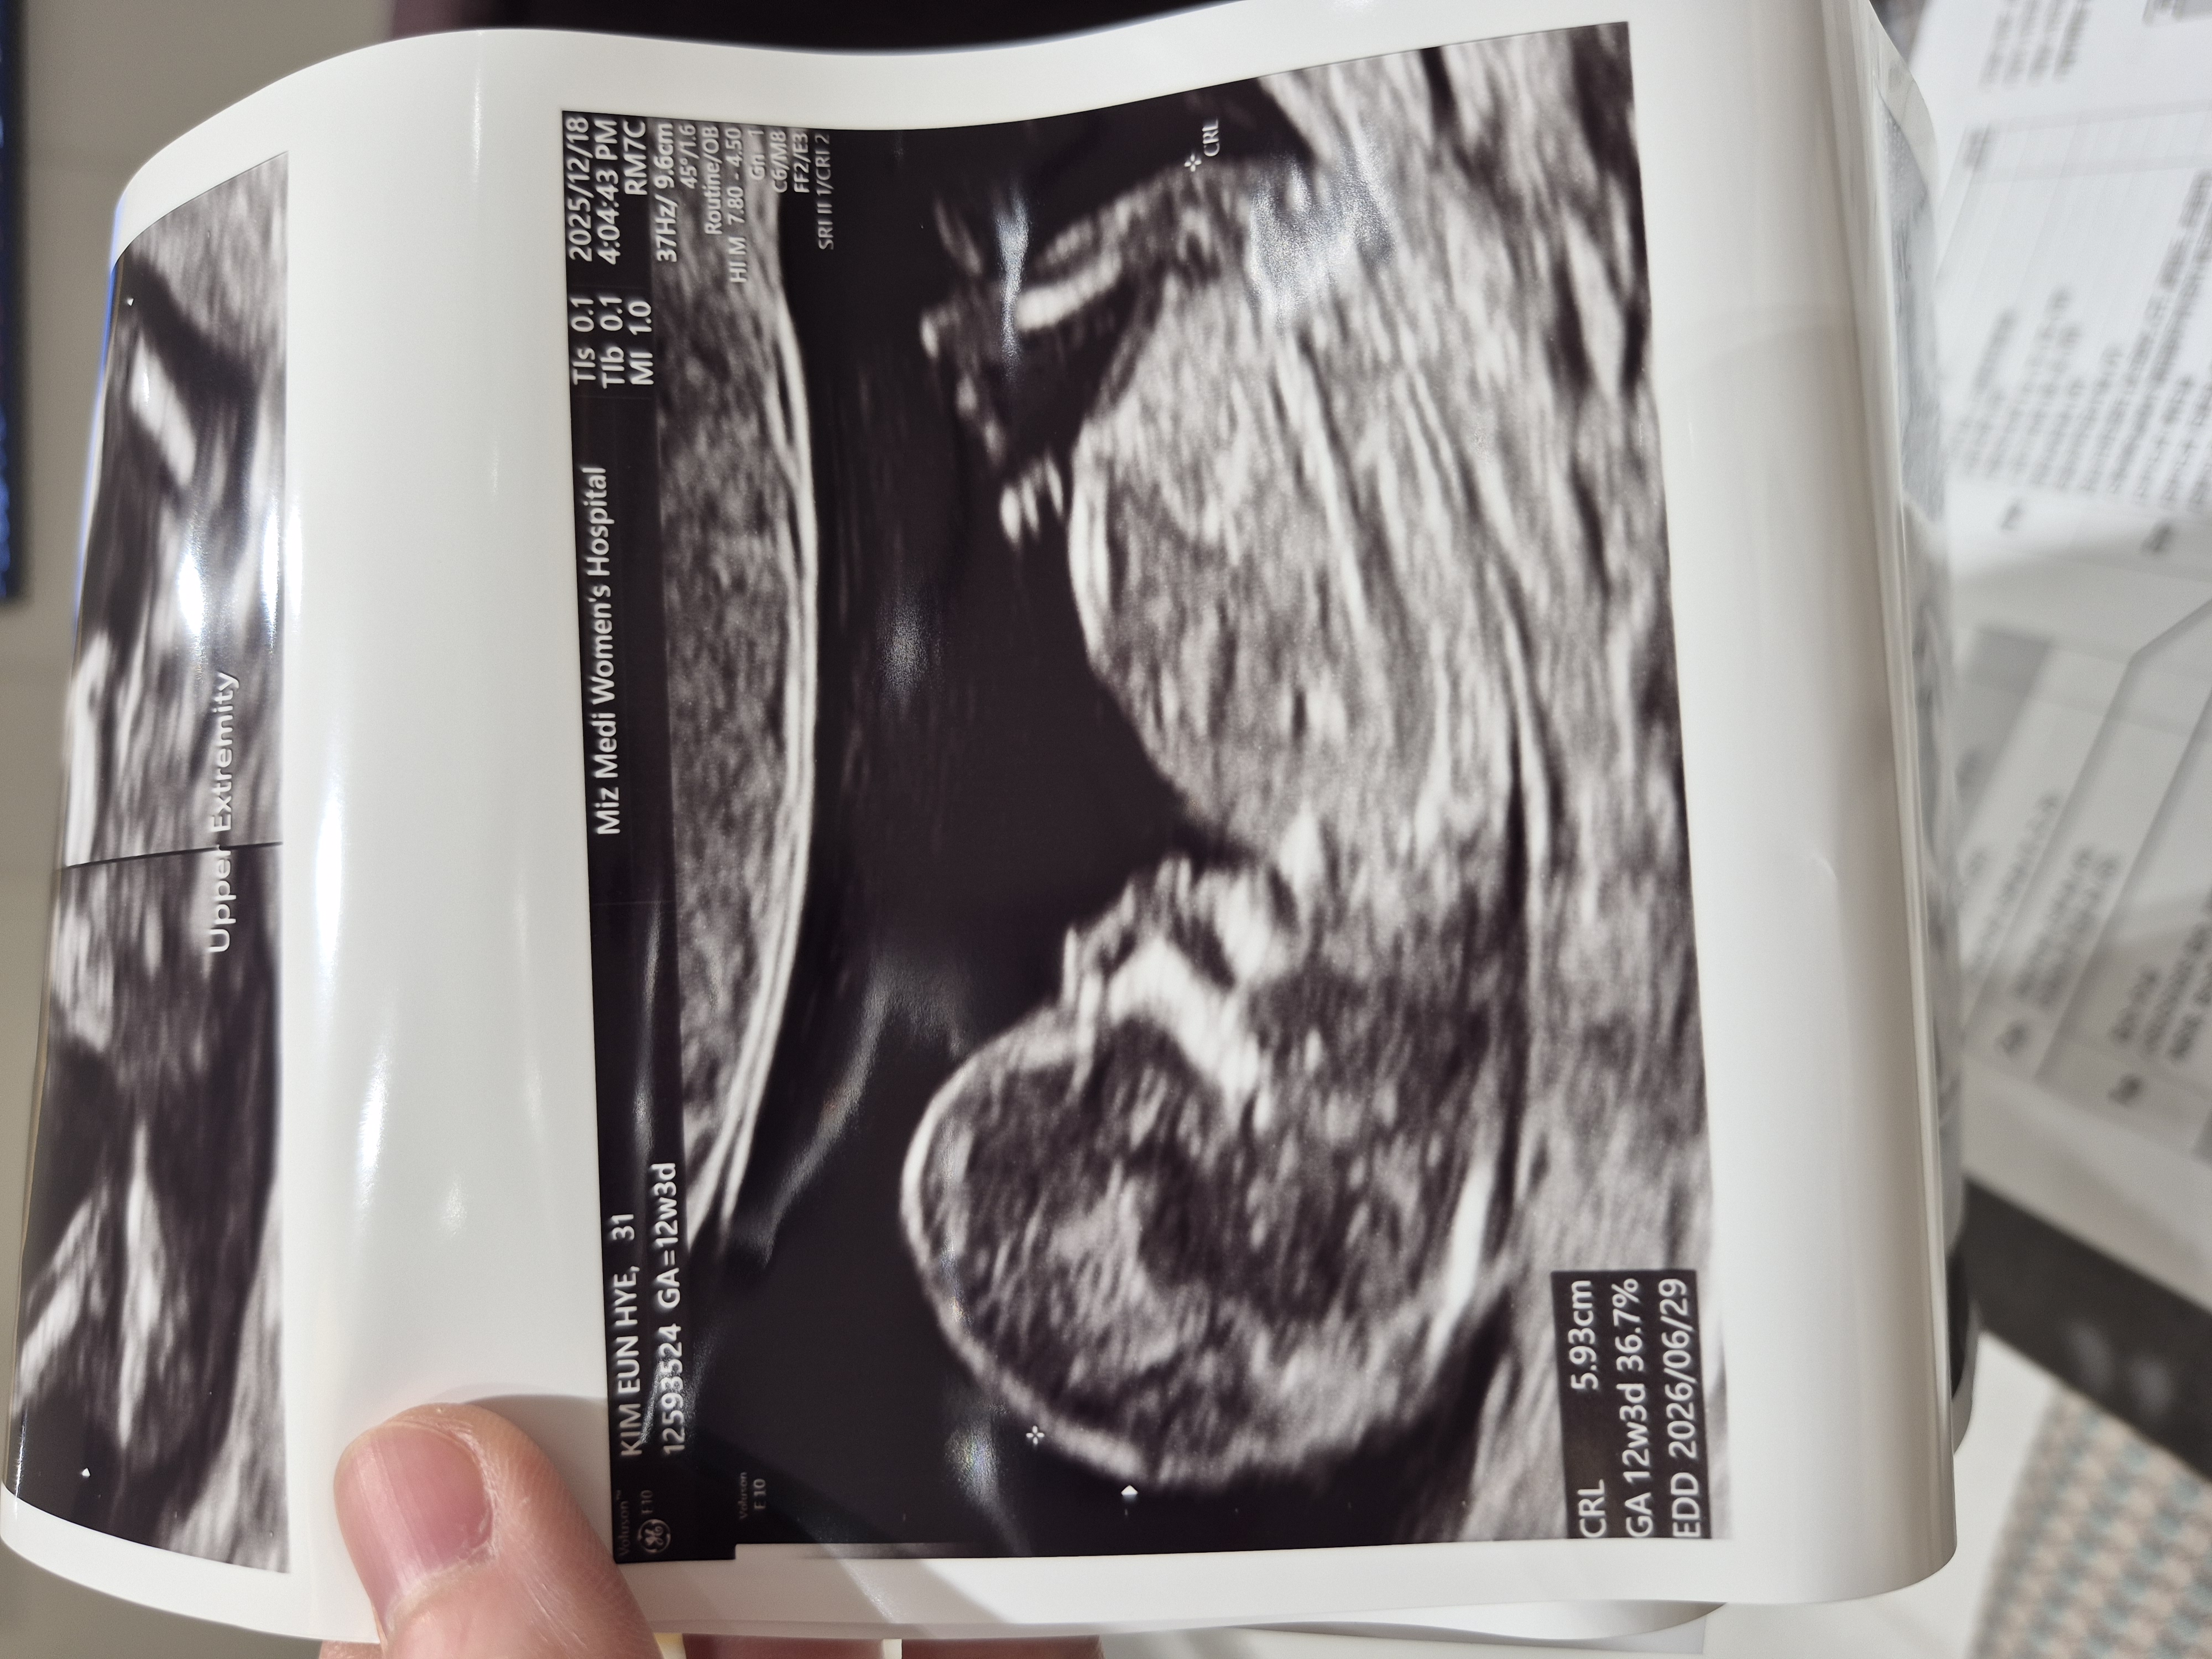

2026년 6월 베동

아직 성별은 모르는거죠??

12주 됐고 성별이 궁금한데 병원에선 아직 성별을 모른데요ㅠ